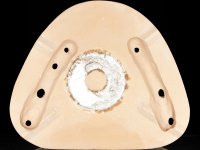

Realizado o diagnóstico e tomada a decisão quanto ao tratamento a executar, tornou-se importante definir qual a sequência de trabalho a adotar no sentido de conseguir a reabilitação da D.V.O. (V.D.O), de forma progressiva e equilibrada. Na primeira fase fez-se uma pré-impressão da arcada inferior com silicone tipo “putty” e em seguida realizou-se o preparo dentário de todo o sector posterior. O preparo para os overlays foi feito coronalmente à linha amelo cementaria no sentido de ser o mais conservador possível. A impressão foi feita com técnica de dupla mistura após afastamento gengival realizado com pasta de caulino. A provisória foi realizada com resina composta de polimerização dual. Em laboratório foram realizados os overlays após se ter aberto ligeiramente (1,5mm) a D.V.O. nos modelos montados em articulador semi-ajustável. Simultaneamente o sector antero-inferior foi encerado no sentido de acompanhar este aumento da D.V.O. Também foi confecionada uma chave de silicone translucido para posterior confeção dos provisórios antero-inferiores. Em boca foi primeiro realizada a provisionalização dos dentes anteriores utilizando resina composta previamente aquecida após preparação das superfícies dentárias para a adesão. Foi colocado o dique de borracha para promover o isolamento absoluto e posteriormente foram colados os overlays. Em laboratório foi realizada nova chave de silicone para confecionar os provisórios antero-superiores. Seguidamente em boca foram preparados os seis dentes antero-superiores após colocação do fio de afastamento gengival. Feita a preparação adequada das superfícies dentárias foi realizada a impressão com técnica de dupla mistura e a respetiva provisória. Em laboratório foram confecionadas 6 facetas feldespáticas num modelo de trabalho tipo “Geller”. A provisória foi removida e as facetas foram coladas em boca utilizando um isolamento relativo competente. Esta opção foi tomada em virtude de uma prévia experiencia negativa com a colocação do dique de borracha na mandibula. Após a colagem dos laminados antero-superiores foram dadas 12 semanas para avaliar a adaptação do paciente à nova situação e então iniciar a confeção das facetas antero-inferiores. Após colocação do fio de afastamento gengival. foram feitos os preparos dentários adequados e em seguida foi feita a impressão. Também foi feita a preparação do dente 3.4 que, entretanto, tinha sofrido uma fratura do overlay. As facetas e a restauração do 3.4 foram realizadas num modelo de trabalho tipo “Geller”. Após remoção da provisória, as facetas foram coladas em boca, utilizando um isolamento relativo pelas razões apontadas anteriormente. Após colocação do trabalho o paciente foi reabilitado por outros colegas com um implante na zona do 2.6 e substituição da coroa aparafusada sobre o implante colocado no local do 3.5. Posteriormente surgiram fraturas nos overlays dos dentes 4.7 e 3.7 que foram reabilitados com overlays em Zr.